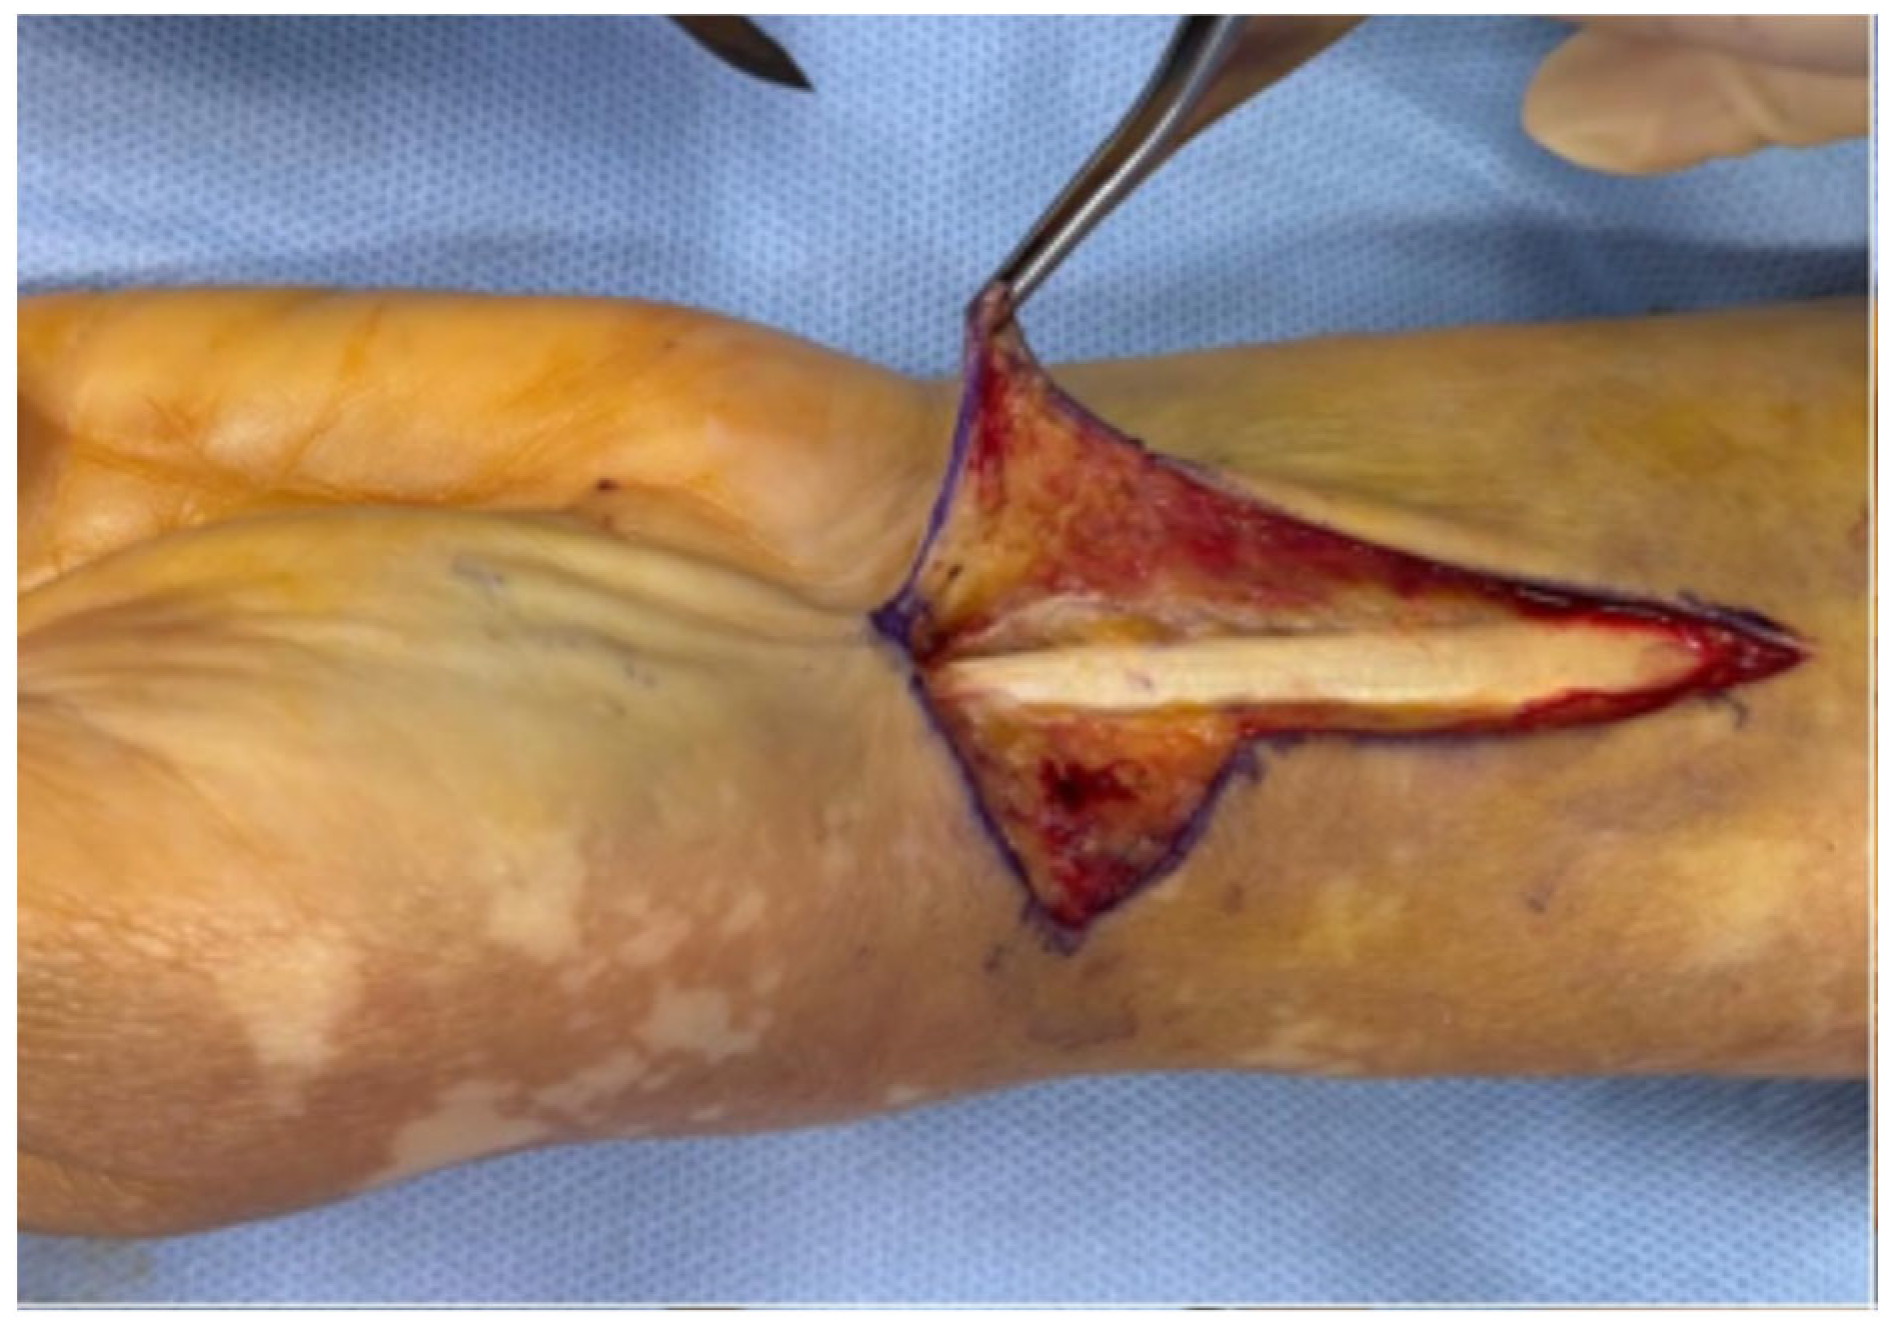

A skin incision is made directly over the flexor carpi radialis (FCR) tendon, extending approximately 6–8 cm. Distally, the incision continues in a zig-zag configuration, beginning at least 1.5 cm proximal to the radial styloid and directed towards it, with the apex of the “V” positioned near—but not directly over—the styloid process to prevent exposure of the radial artery. The distal tip of the “V” lies proximal to the wrist flexion crease, corresponding to the most distal course of the FCR tendon (Figure 1).

In contrast to Orbay’s original zig-zag approach [3], which traverses the wrist flexion creases, the authors propose a modified version in which the apex of the “V” is positioned near the radial styloid (Figure 1). This modification provides superior exposure of the radial styloid compared with Orbay’s method. By directly aligning the apex over the styloid process, the surgeon achieves immediate visualization of this structure without the need for excessive traction on adjacent soft tissues. Consequently, the radial artery—although clearly visible—is effectively protected, as it remains outside the direct operative field and is shielded from potential iatrogenic injury caused by surgical instruments.

Figure 1. (a) Orbay incision; (b) Authors modified incision.